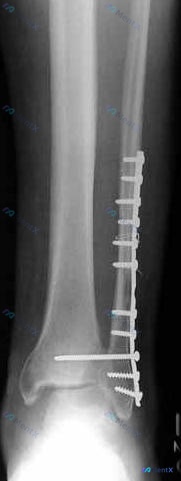

整理到一个右前臂尺桡骨骨折术后的影像学病例,资料如下: 基本背景 右侧前臂(桡骨与尺骨)双骨折术后内固定状态。 影像学表现 1. 内固定:桡骨、尺骨干均可见钢板+螺钉固定,钢板跨越骨干中段,目前钢板螺钉位置固定,未见明显移位、松动或断裂征象。 2. 骨折愈合:骨折断端处骨痂形成尚不明显(骨痂影较淡)...